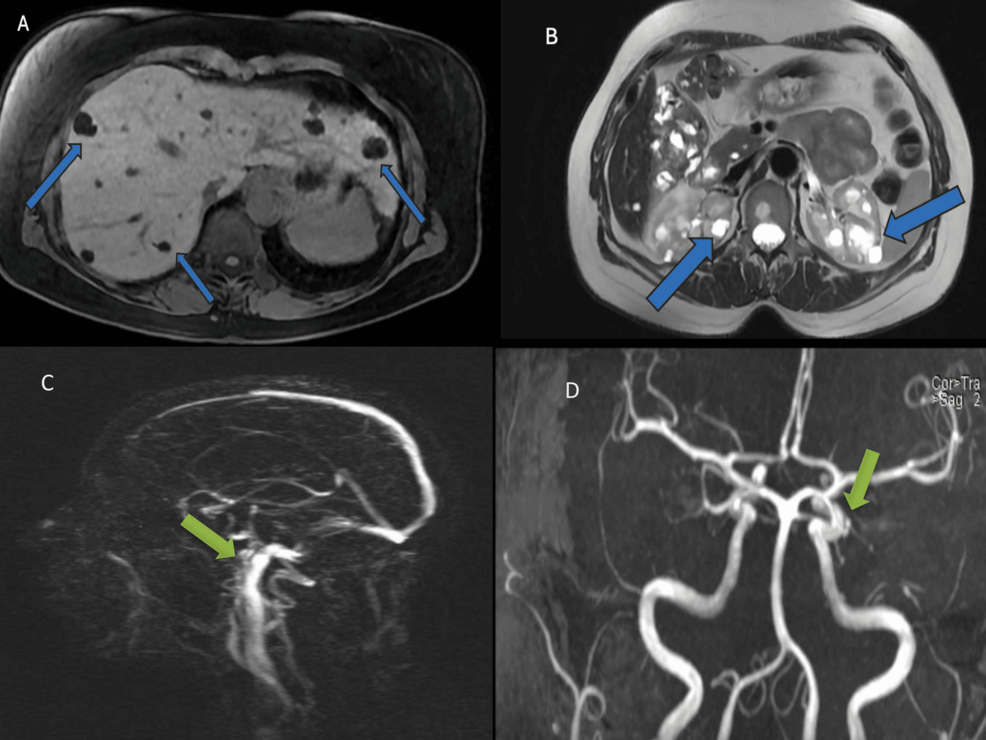

Invasive aspergillosis (IA) remains a serious and often fatal infection despite advances in diagnostics and antifungal therapy. Although mold-active triazoles have long been recommended as first-line therapy, liposomal amphotericin B continues…